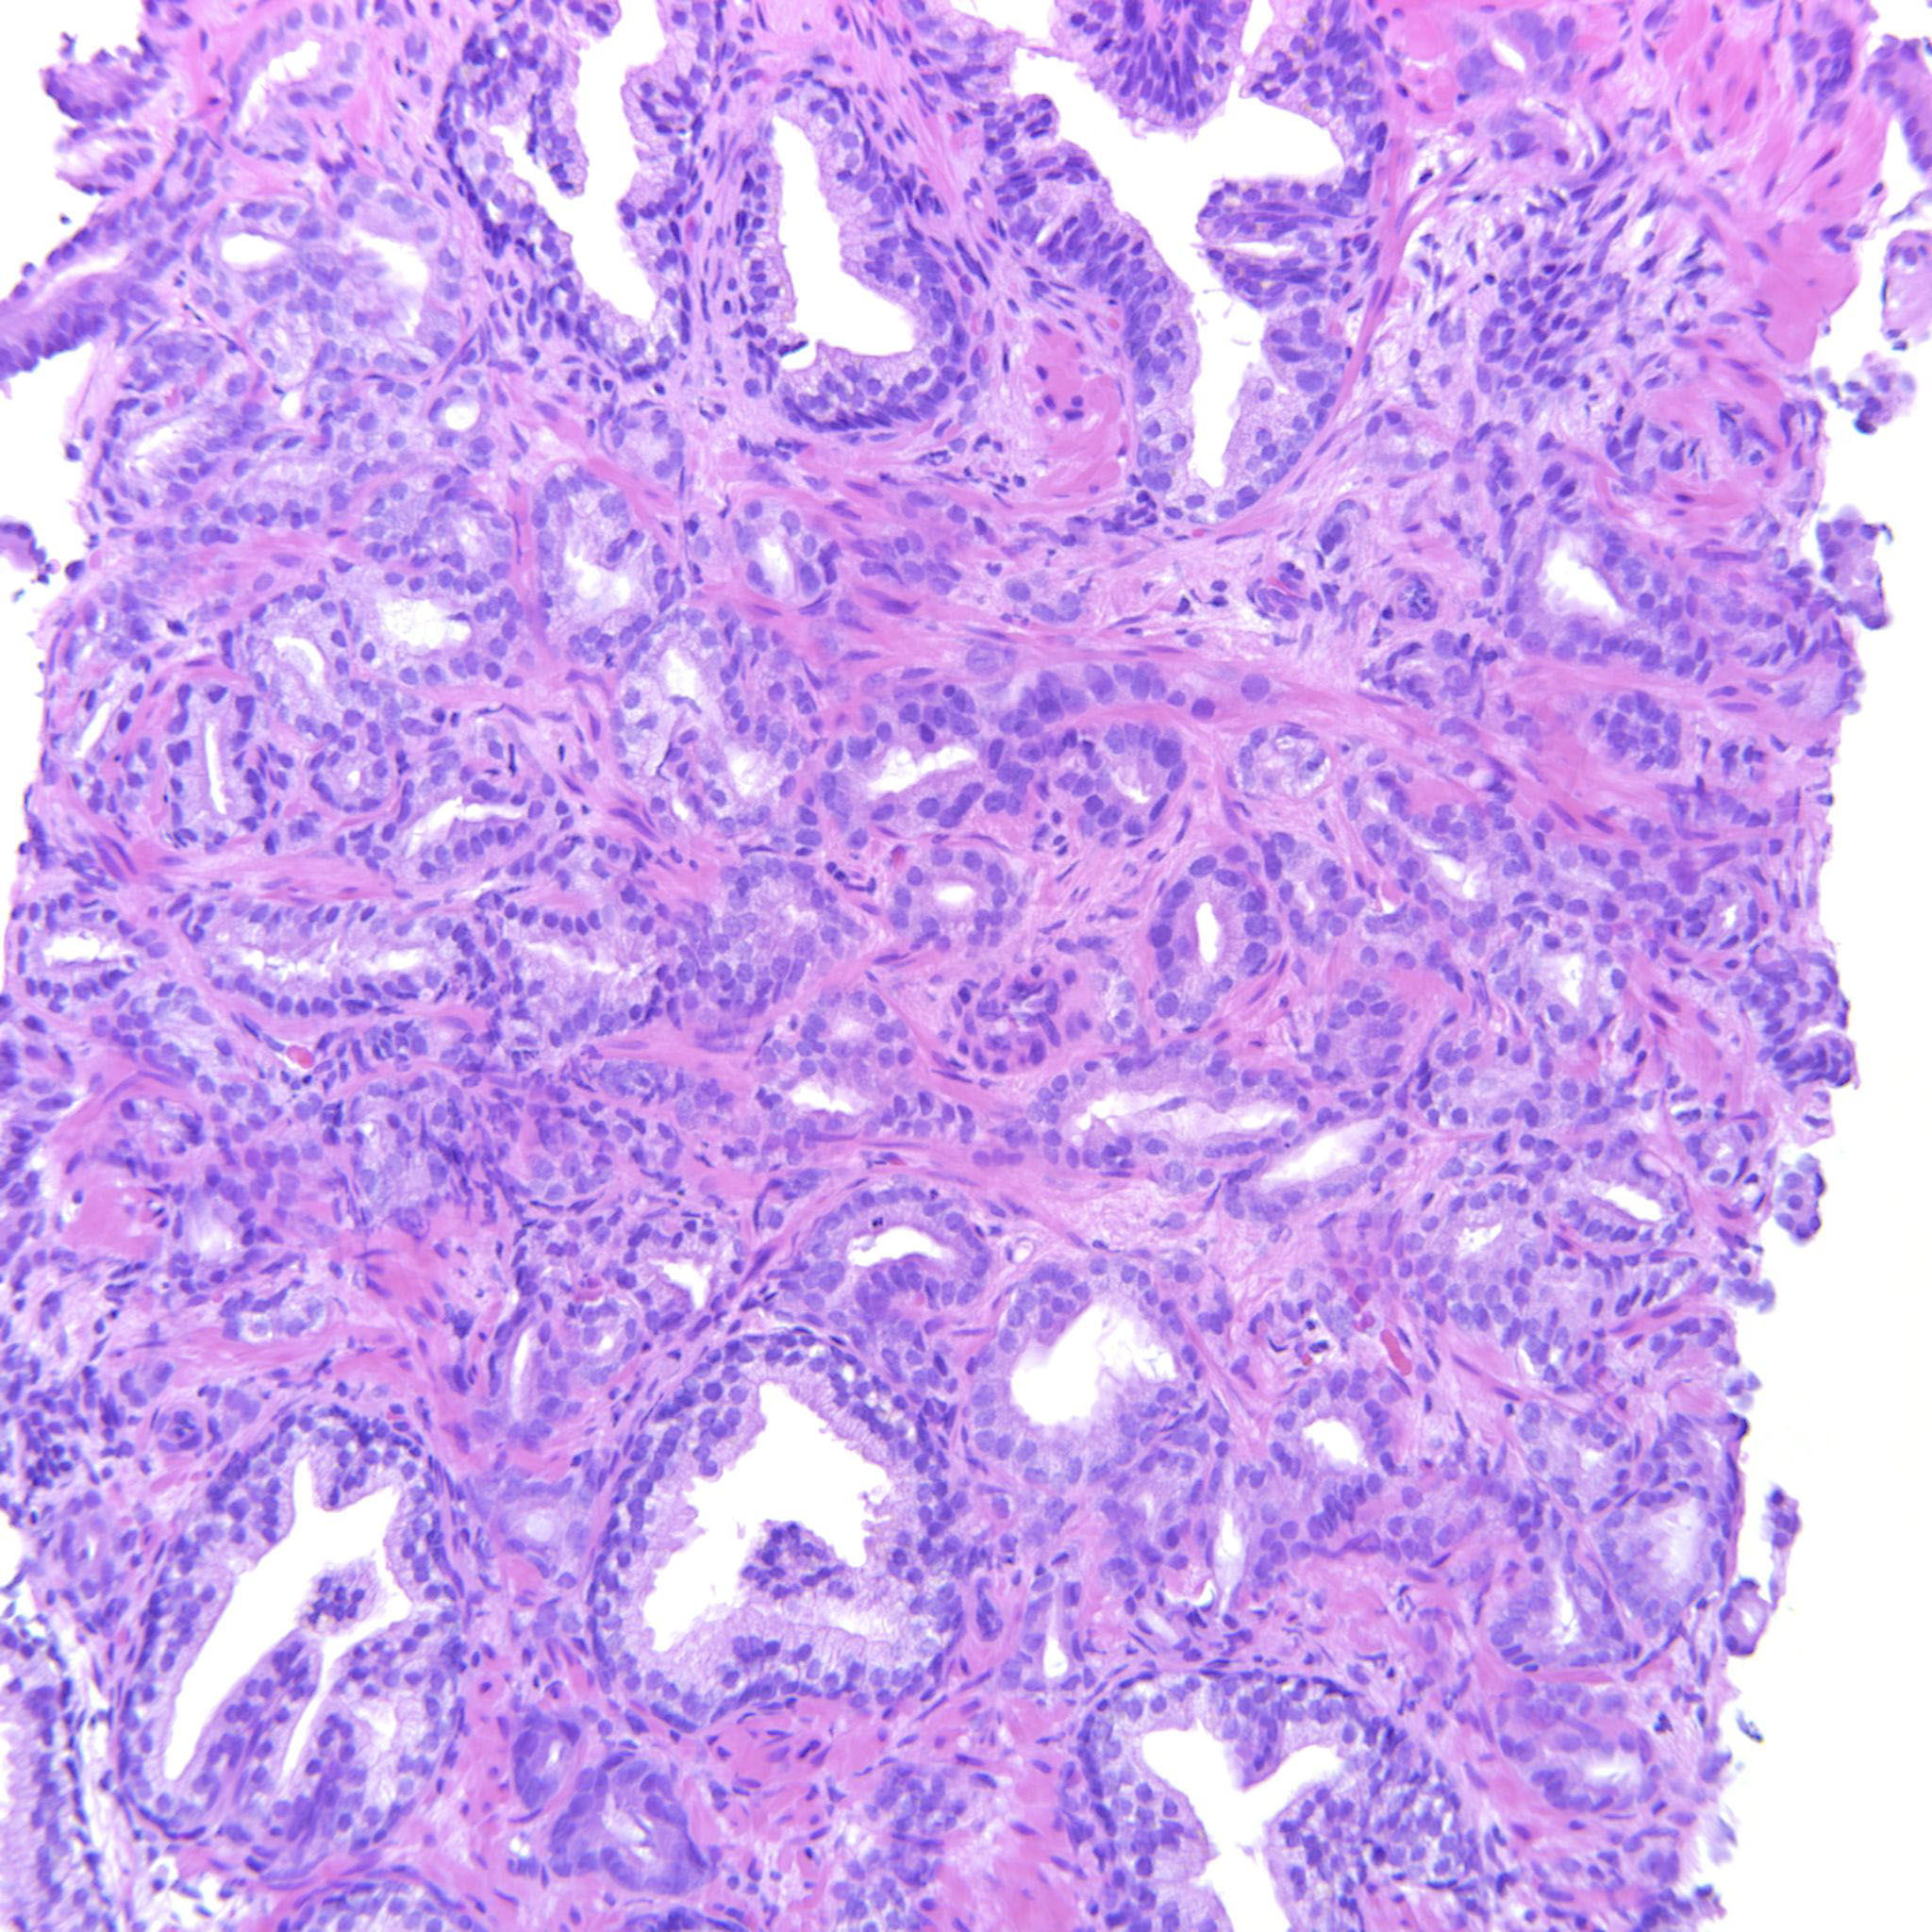

Consensus grade: GS 3+4=7 (ISUP 2)

User Diagnosis Difficulty Comment

Pathologist 1 GS 3+4=7 (ISUP 2) Borderline higher

Glands crowded but also focally fused

Case description (by case creator):

Some images only contain GP3 but there are also areas with poorly formed and fused glands justifying 347.